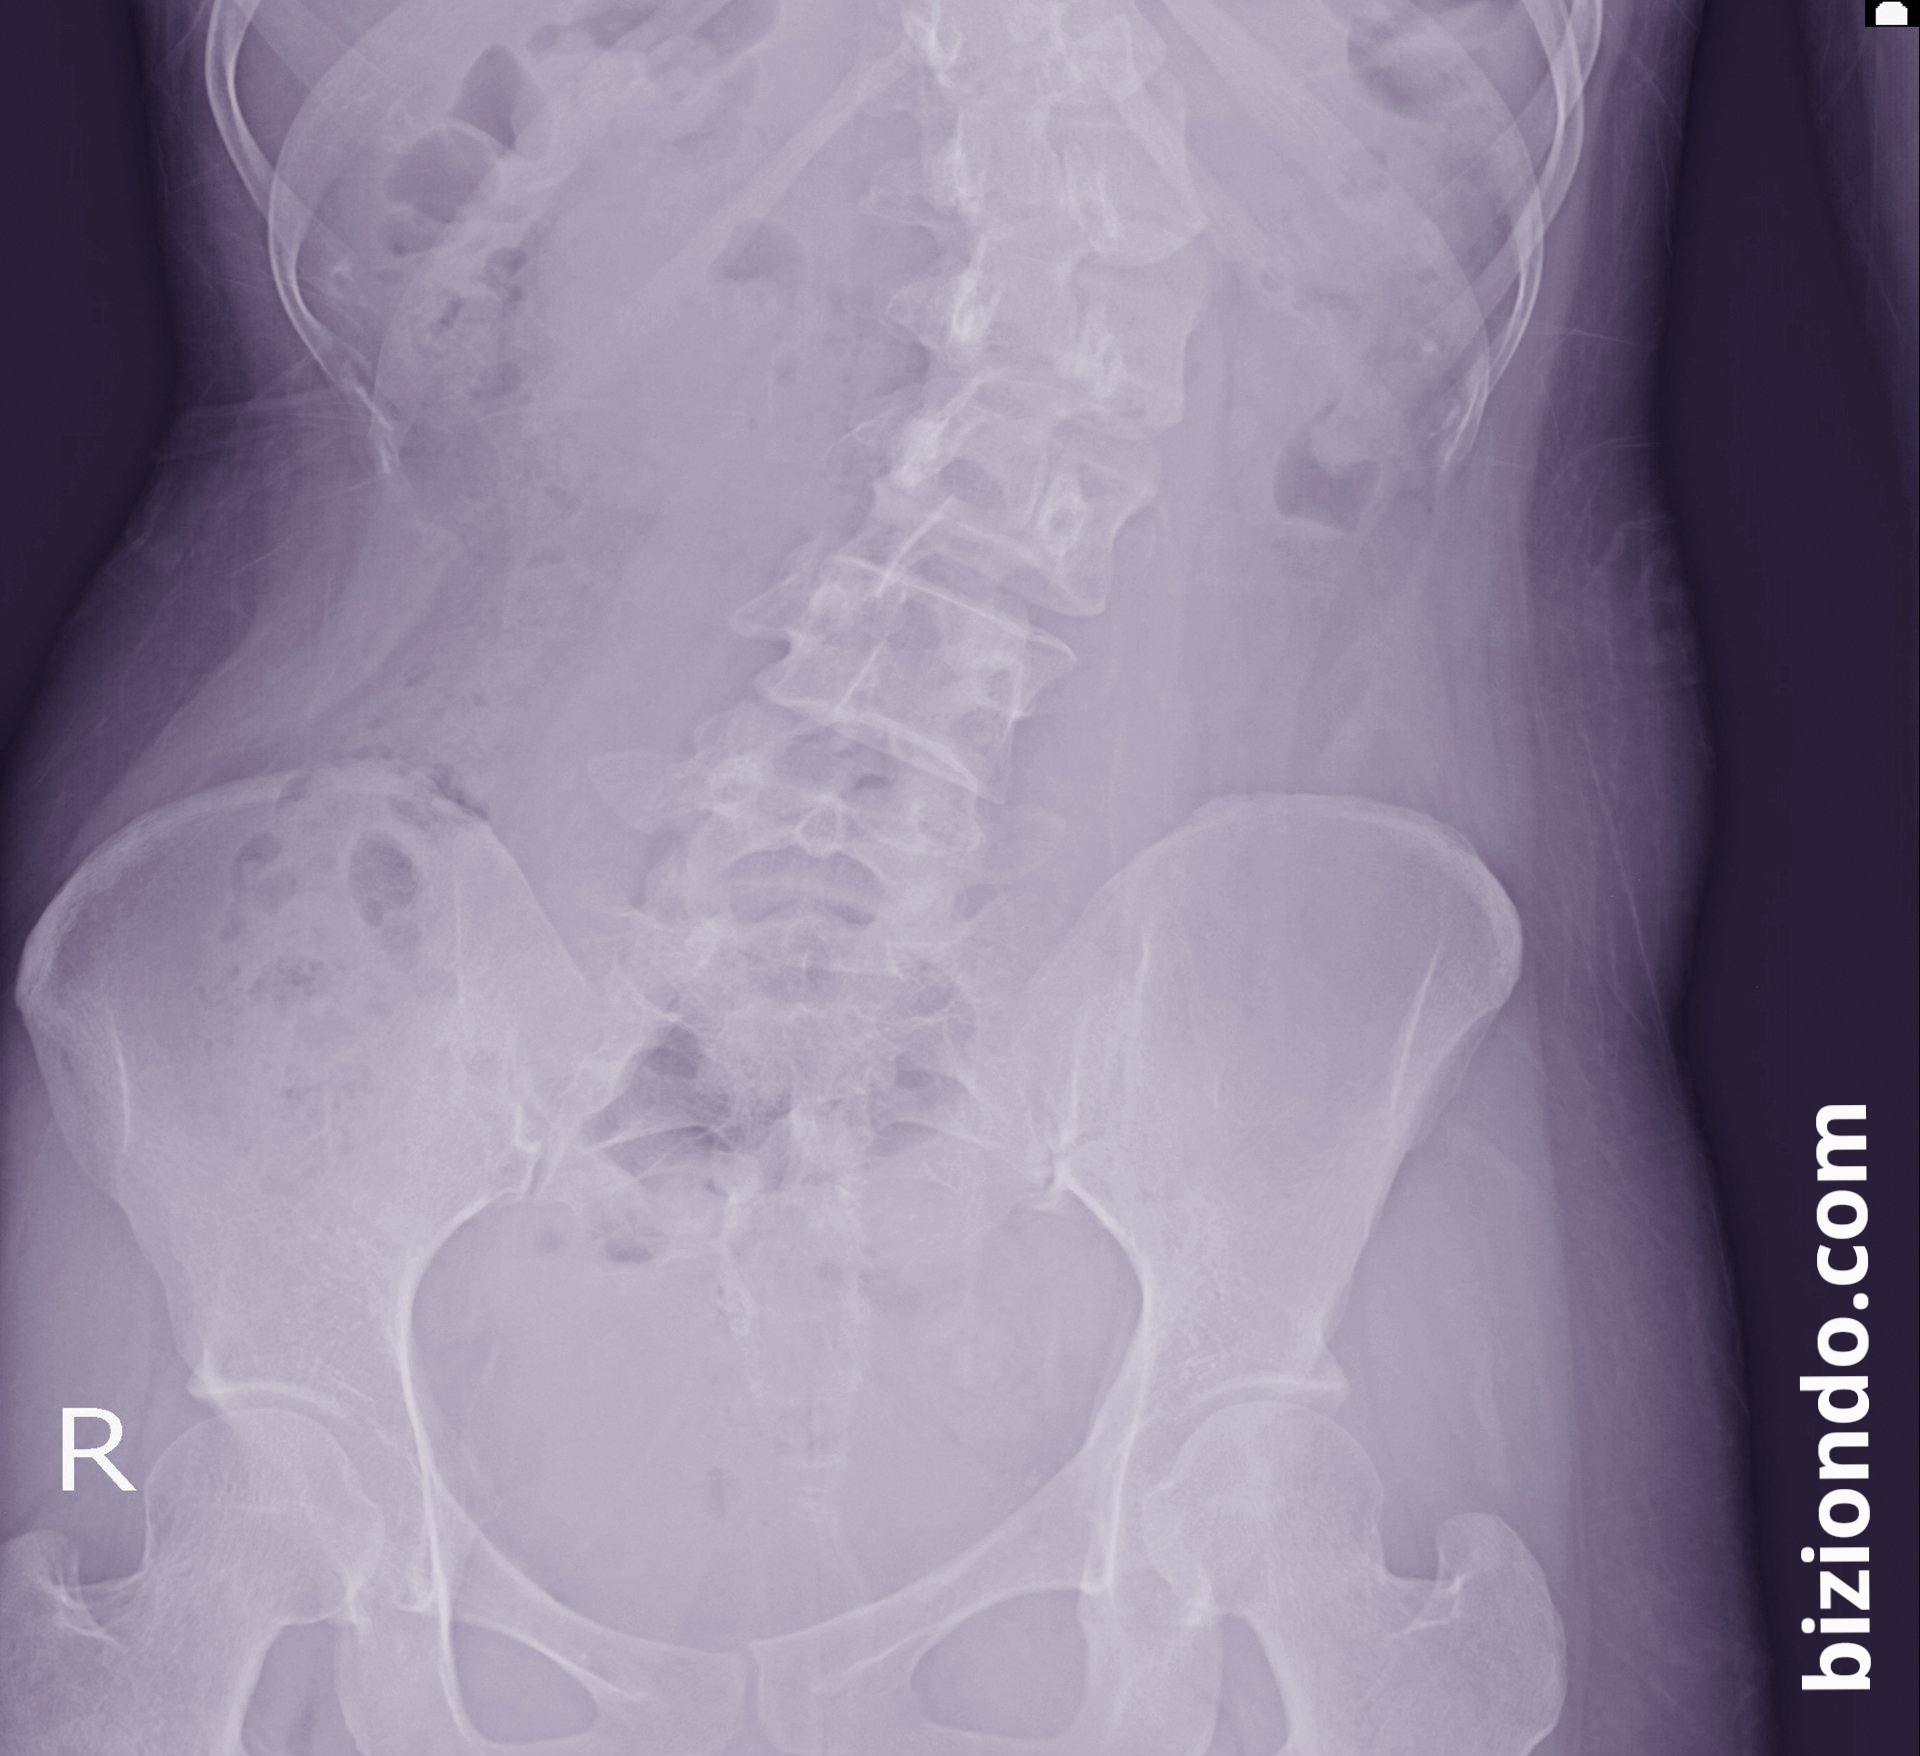

Radiografías y estudios por imagen

La radiografía es el método más utilizado. En Biziondo contamos con estudios avanzados que permiten medir con precisión el ángulo de curvatura (ángulo de Cobb) y diseñar un plan de tratamiento personalizado.